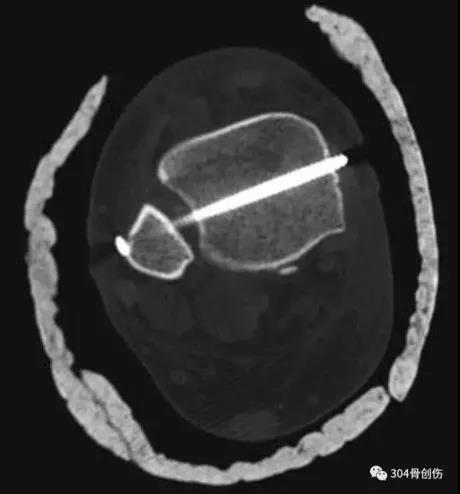

术前CT